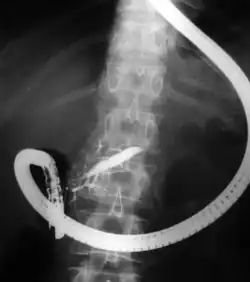

Endoscopic retrograde cholangiopancreatography (ERCP) is a technique that combines the use of endoscopy and fluoroscopy to diagnose and treat certain problems of the biliary or pancreatic ductal systems. It is primarily performed by highly skilled and specialty trained gastroenterologists. Through the endoscope, the physician can see the inside of the stomach and duodenum, and inject a contrast medium into the ducts in the biliary tree and/or pancreas so they can be seen on radiographs.

The patient is sedated or anaesthetized. Then a flexible camera (endoscope) is inserted through the mouth, down the esophagus, into the stomach, through the pylorus into the duodenum where the ampulla of Vater (the union of the common bile duct and pancreatic duct) exists. The sphincter of Oddi is a muscular valve that controls the opening to the ampulla. The region can be directly visualized with the endoscopic camera while various procedures are performed. A plastic catheter or cannula is inserted through the ampulla, and radiocontrast is injected into the bile ducts and/or pancreatic duct. Fluoroscopy is used to look for blockages, or other lesions such as stones.[8][9]

When needed, the sphincters of the ampulla and bile ducts can be enlarged by a cut (sphincterotomy) with an electrified wire called a sphincterotome for access into either so that gallstones may be removed or other therapy performed.[10]

Other procedures associated with ERCP include the trawling of the common bile duct with a basket or balloon to remove gallstones and the insertion of a plastic stent to assist the drainage of bile.[11] Also, the pancreatic duct can be cannulated and stents be inserted.